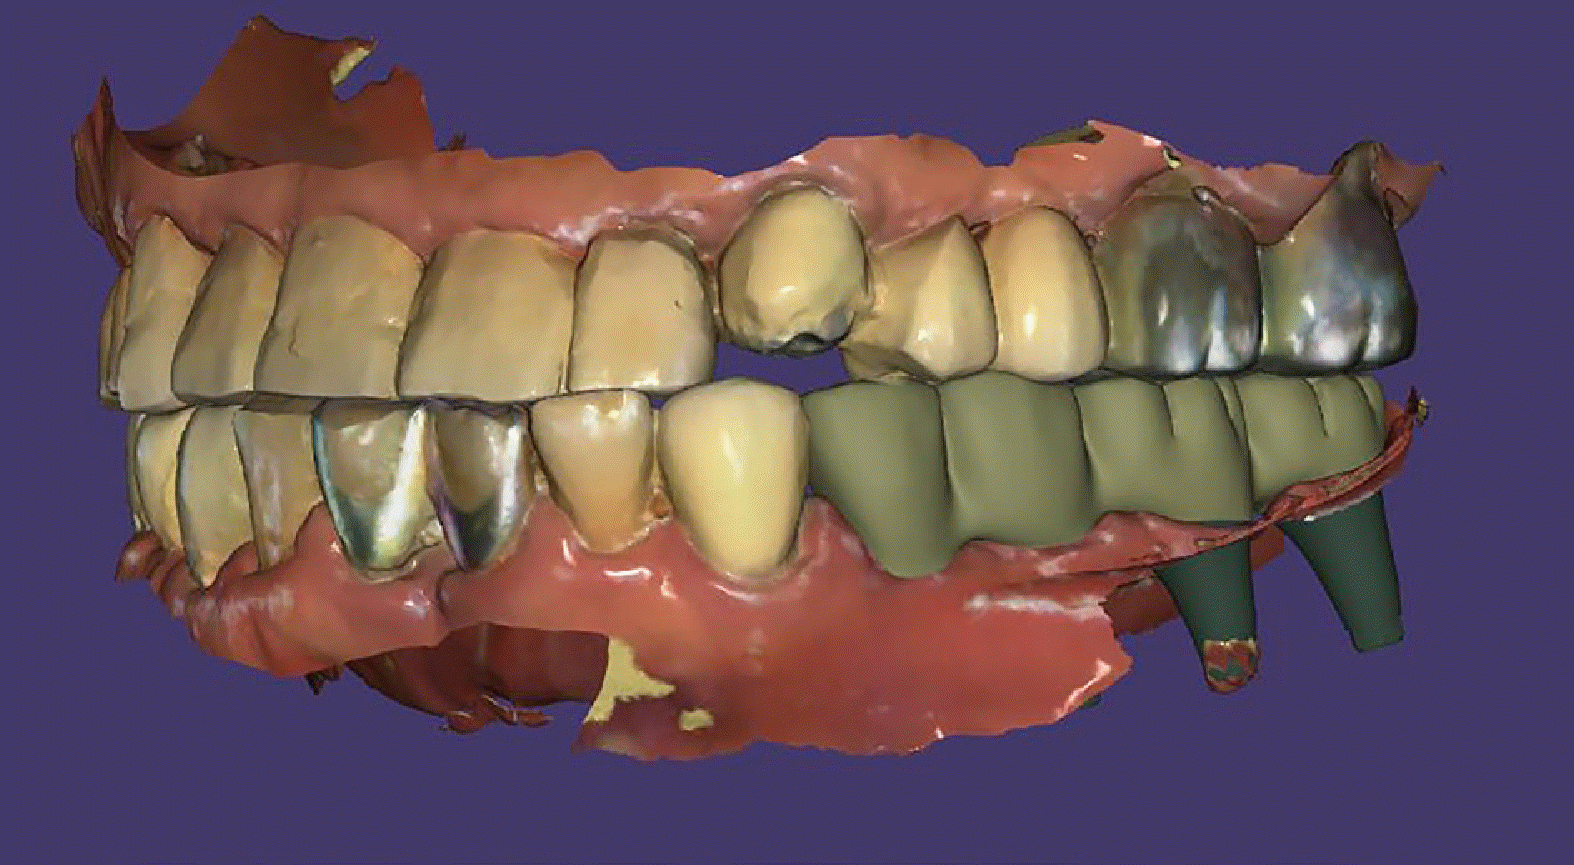

Fig. 4

Images of the provisional crowns for both anterior and posterior teeth are presented. (A - C) Delivery of provisional crowns on maxillary anterior and mandibular posterior areas in a proper CR position, (D) A digital image depicting the provisional state is shown.

Osstem TS III fixtures (Osstem Implant Co., Seoul, South Korea) were placed at #36 and #37, and Dentis S-Clean SQ-SL implants (Dentis Co., Daegu, South Korea) at #34, 35, 43, 45, 46, and 47. Immediately post-surgery, Highness® base abutments were connected with 30 Ncm torque, followed by attachment of Highness® scan bodies using hand torque. Digital impressions of the maxillary and mandibular dentitions, including a buccal bite scan reflecting the established anterior bite stop, were obtained using Primescan (Sirona Dental Systems GmbH, Bensheim, Germany) and analyzed with Exocad software (Exocad GmbH, Darmstadt, Germany). The following day, polymethyl methacrylate (PMMA) Highness® provisional restorations were delivered with hand torque, establishing partial group function occlusion during lateral excursions (Fig. 3, 4).